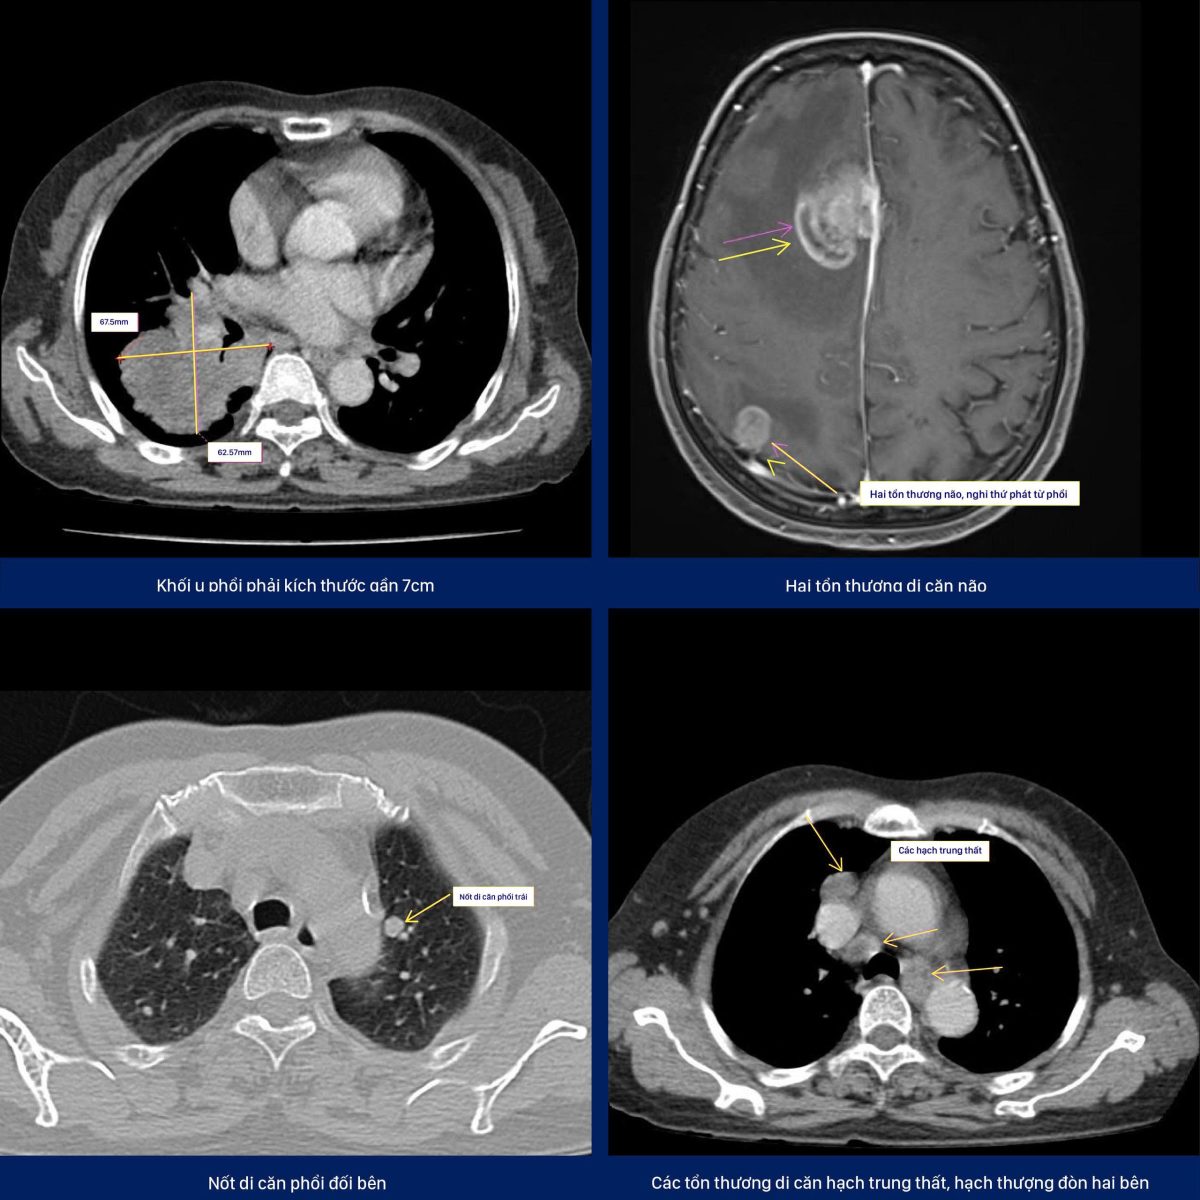

Khi đến Thiện Nhân, bệnh nhân được chụp MRI sọ não 3.0 Tesla Siemens Lumina, ghi nhận tổn thương nghi di căn não. Để tìm ổ nguyên phát, bác sĩ đã chỉ định chụp CT ngực.

Kết quả: phát hiện khối u phổi phải gần 7cm, di căn hạch trung thất, di căn phổi đối bên, di căn não – chẩn đoán ung thư phổi giai đoạn cuối.

– MRI 3.0 Tesla Siemens Lumina (Đức): Tái tạo hình ảnh não chi tiết, giúp phát hiện tổn thương di căn mà X-quang hoặc siêu âm khó nhận ra.

– Chụp CT ngực liều thấp: Công nghệ hiện đại cho phép phát hiện khối u nhỏ dưới 1cm, với liều tia thấp hơn chụp CT thông thường, hạn chế nguy cơ phơi nhiễm tia X nhưng vẫn đảm bảo độ chính xác cao.